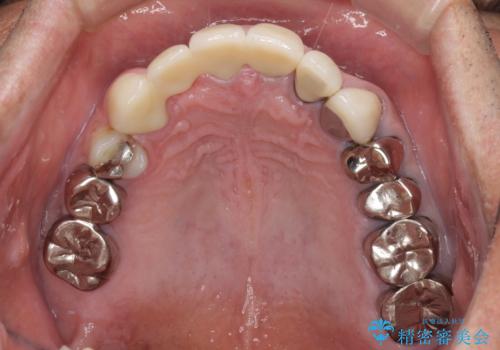

歯肉が少し退縮していたため、補綴治療のやり直しにより歯が少し長く見えるようになりましたが、自然な口元に仕上がり、患者様には大変満足していただきました。

定期的にラグビーをされるとのことなので、マウスピースの装着をかかさないようにお伝えしました。